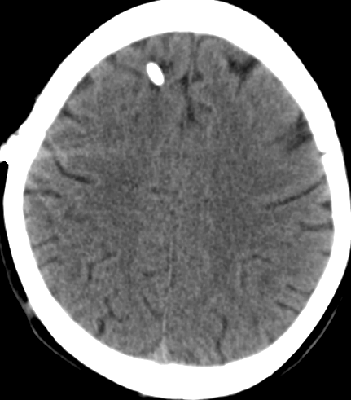

2013-8-8 CT

2013-8-7 脑室腹腔分流术,初压130

2013-8-8 仍诉头痛

2013-8-10 腰穿测压150mmH2O